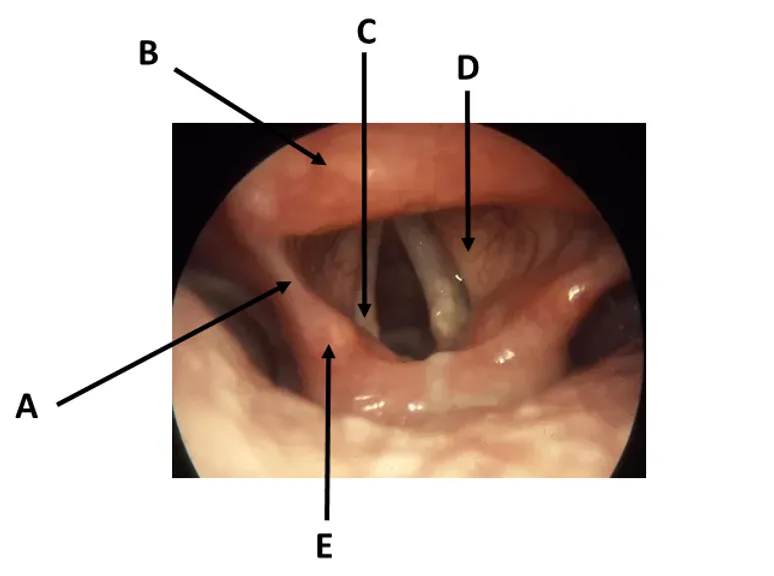

Q1 - Name structures A-E in image 1